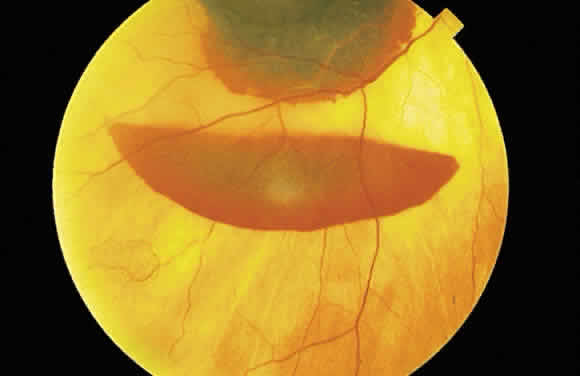

The location of the hemorrhage also may affect is ophthalmoscopic appearance. Fresh hemorrhage between the retinal pigment epithelium and Bruch's membrane may appear brown or red-black, in contrast with the bright red color seen in fresh hemorrhages anterior to the pigment epithelium (see Fig. 13A). The location of hemorrhages within the retina also accounts for the shape of the lesion. Blood that accumulates between the nerve fiber layer and the internal limiting membrane (subinternal limiting membrane hemorrhage) (Fig. 57) assumes a shape defined by gravity, meniscus or boat-shaped, when the patient is upright (Fig. 58). The name subinternal limiting membrane hemorrhage is technically ambiguous, since a hemorrhage in the outer plexiform layer also is below (sub) the internal limiting membrane.

Fig. 57. Photomicrograph of a hemorrhage present just beneath the internal limiting membrane. The hemorrhage is delimited on the photomicrograph by arrows.

Fig. 58. Hemorrhage located just beneath the internal limiting membrane with the patient in the upright position. The retinal vessels are visible on the surface of the layered hemorrhage.